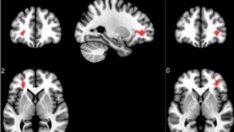

07:25 SINAV DÖNEMİNDE KONTROLSÜZ İLAÇ KULLANIMI ALARM VERİYOR

13:11 YAŞAM ALIŞKANLIKLARINDAKİ DEĞİŞİKLİKLERLE ÖNLEMEK MÜMKÜN